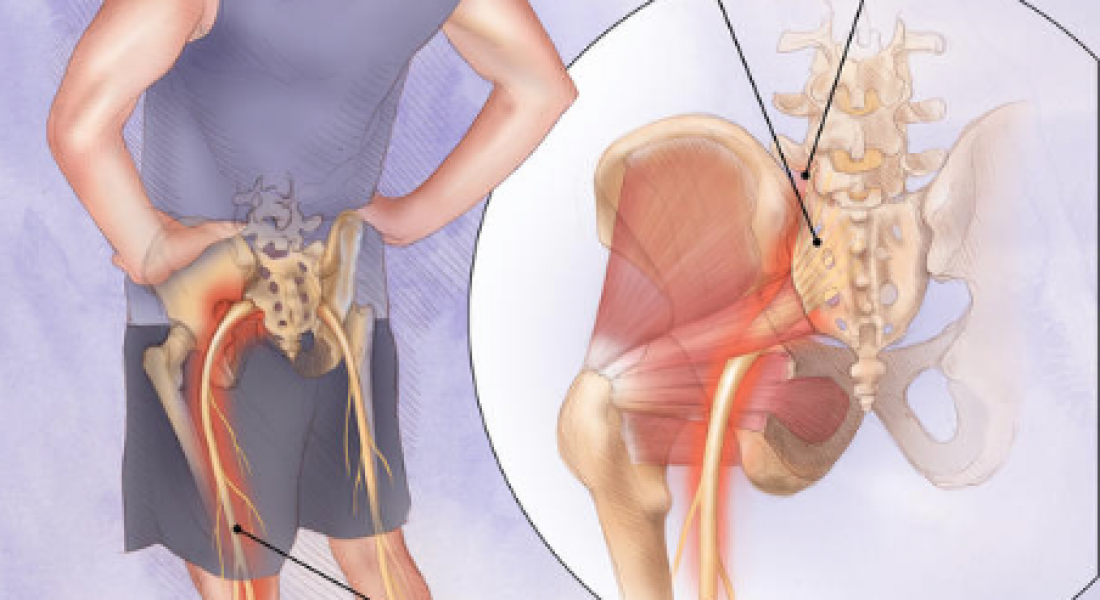

Боль в малом тазу у женщин: Причины и подходы к лечению